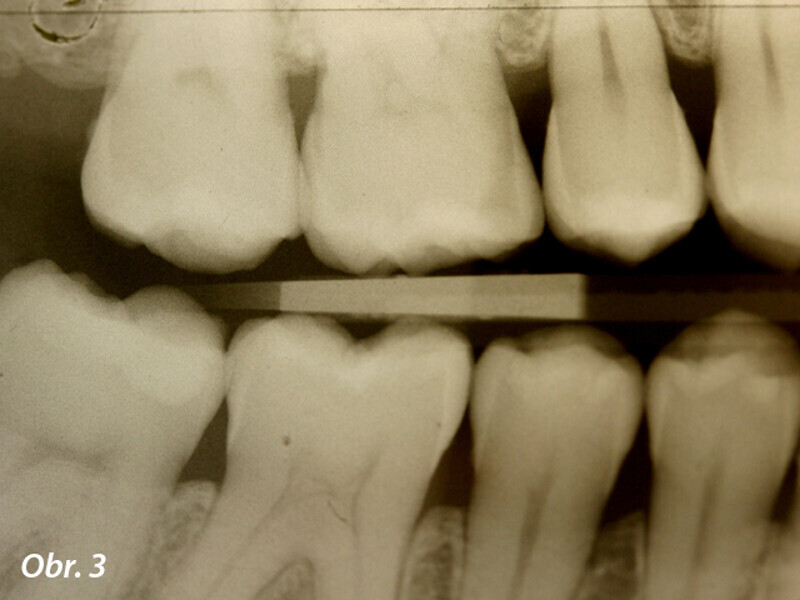

Funkční, anatomická a estetická harmonie s novým kompozitním materiálem Enamel Plus HRi